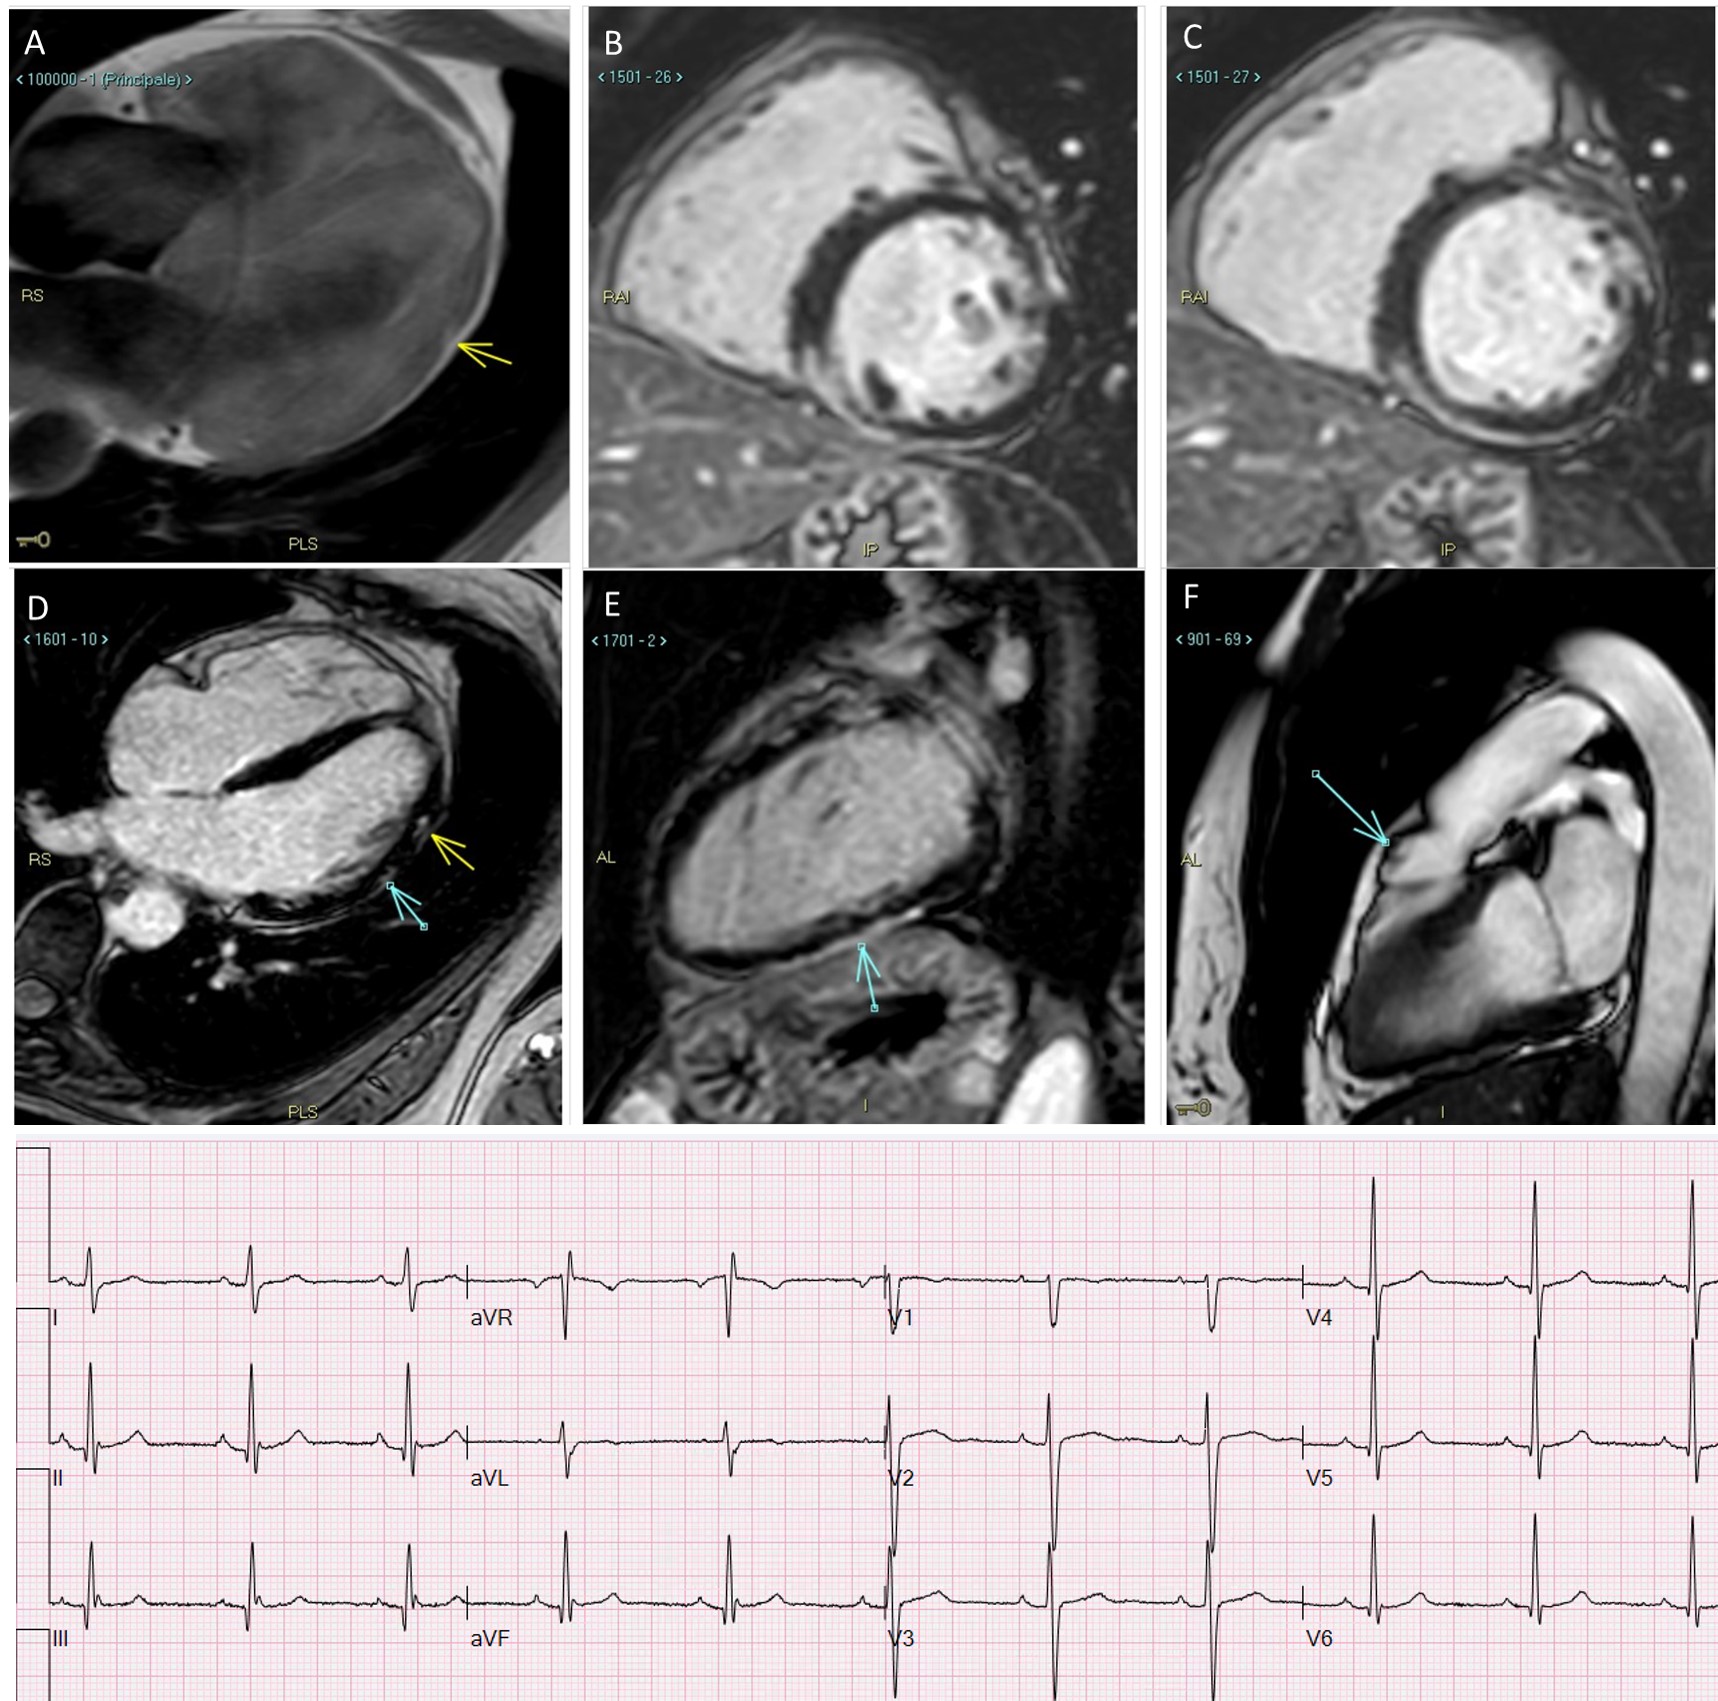

This review on Arrhythmogenic Cardiomyopathy (ACM) focuses on its diagnostic challenges, on the debated role of risk-stratification of sudden cardiac death, and reports the outcome of ICD treatment for sudden death prevention in all cardiac phenotypes. ACM is a general term that encompasses a group of diseases different amongst themselves depending on type of pathologic involvement of the heart, aetiology, and genetics. While it is rationale to assign a specific nosographic classification to entities having a homogeneous genetic background (mutations of the same gene/group of genes) resulting in a common clinical phenotype (Figs. 1,2), it is much more clinically challenging to classify a disease whose phenotypic appearance is the outcome of several unlinked genetic diseases with different pathogenic mechanisms. Even more difficult is disease classification when different mutations of the same gene are disease-causative in the same organ with different phenotypes (hypertrophic vs arrhythmogenic disease). Debate as to whether a genomic-based classification of diseases or a clinical phenotype-based one is more appropriate is ongoing. We focus on ACM phenotype expressed as right ventricular, biventricular, and left ventricular involvement of the heart caused by progressive replacement of the myocardium by fibrotic or fibro-fatty tissue, which acts as an arrhythmogenic substrate predisposing to life-threatening ventricular arrhythmias and heart failure due to systolic ventricular dysfunction, caused by inherited genetic abnormalities. The earliest clinical manifestations of these diseases are ventricular arrhythmias, typically occurring between the third and the fourth decade, though they represent a relevant cause of sudden death in adolescents, especially in the physically active and in high-level athletes [1]. Sudden cardiac death (SCD) can be the first manifestation in a minority of patients, thereby heightening medical attention in the event ventricular arrhythmias are detected in otherwise healthy and young individuals. Progressive fibrotic replacement of myocardial cells leads to ventricular dysfunction and heart failure (Fig. 3) in the advanced stages of the disease, which can have an extremely different time course across individuals. Several efforts aimed at understanding, diagnose, and manage ACM have been made in the past decades, yet there is an ongoing debate surrounding ACM.

Fig. 3.Progressive fibrofatty replacement of the RV and later of the LV in a patient with PKP2 mutation, detected by serial ECG recordings (A) from age 44 up to 72, implanted in secondary prevention at 66 because of monomorphic VT at 210 bpm. Both ECG and CMR (B) show epicardial, midventricular and also transmural fibrotic involvement of the inferior and the posterior lateral LV wall, mimicking ischemic cardiomyopathy in the absence of coronary artery disease. The RV involvement and the progressive ECG changes along years (transition from a normal pattern to an RV and eventually to extensive LV involvement) hinted at genetic testing for the etiologic diagnosis.